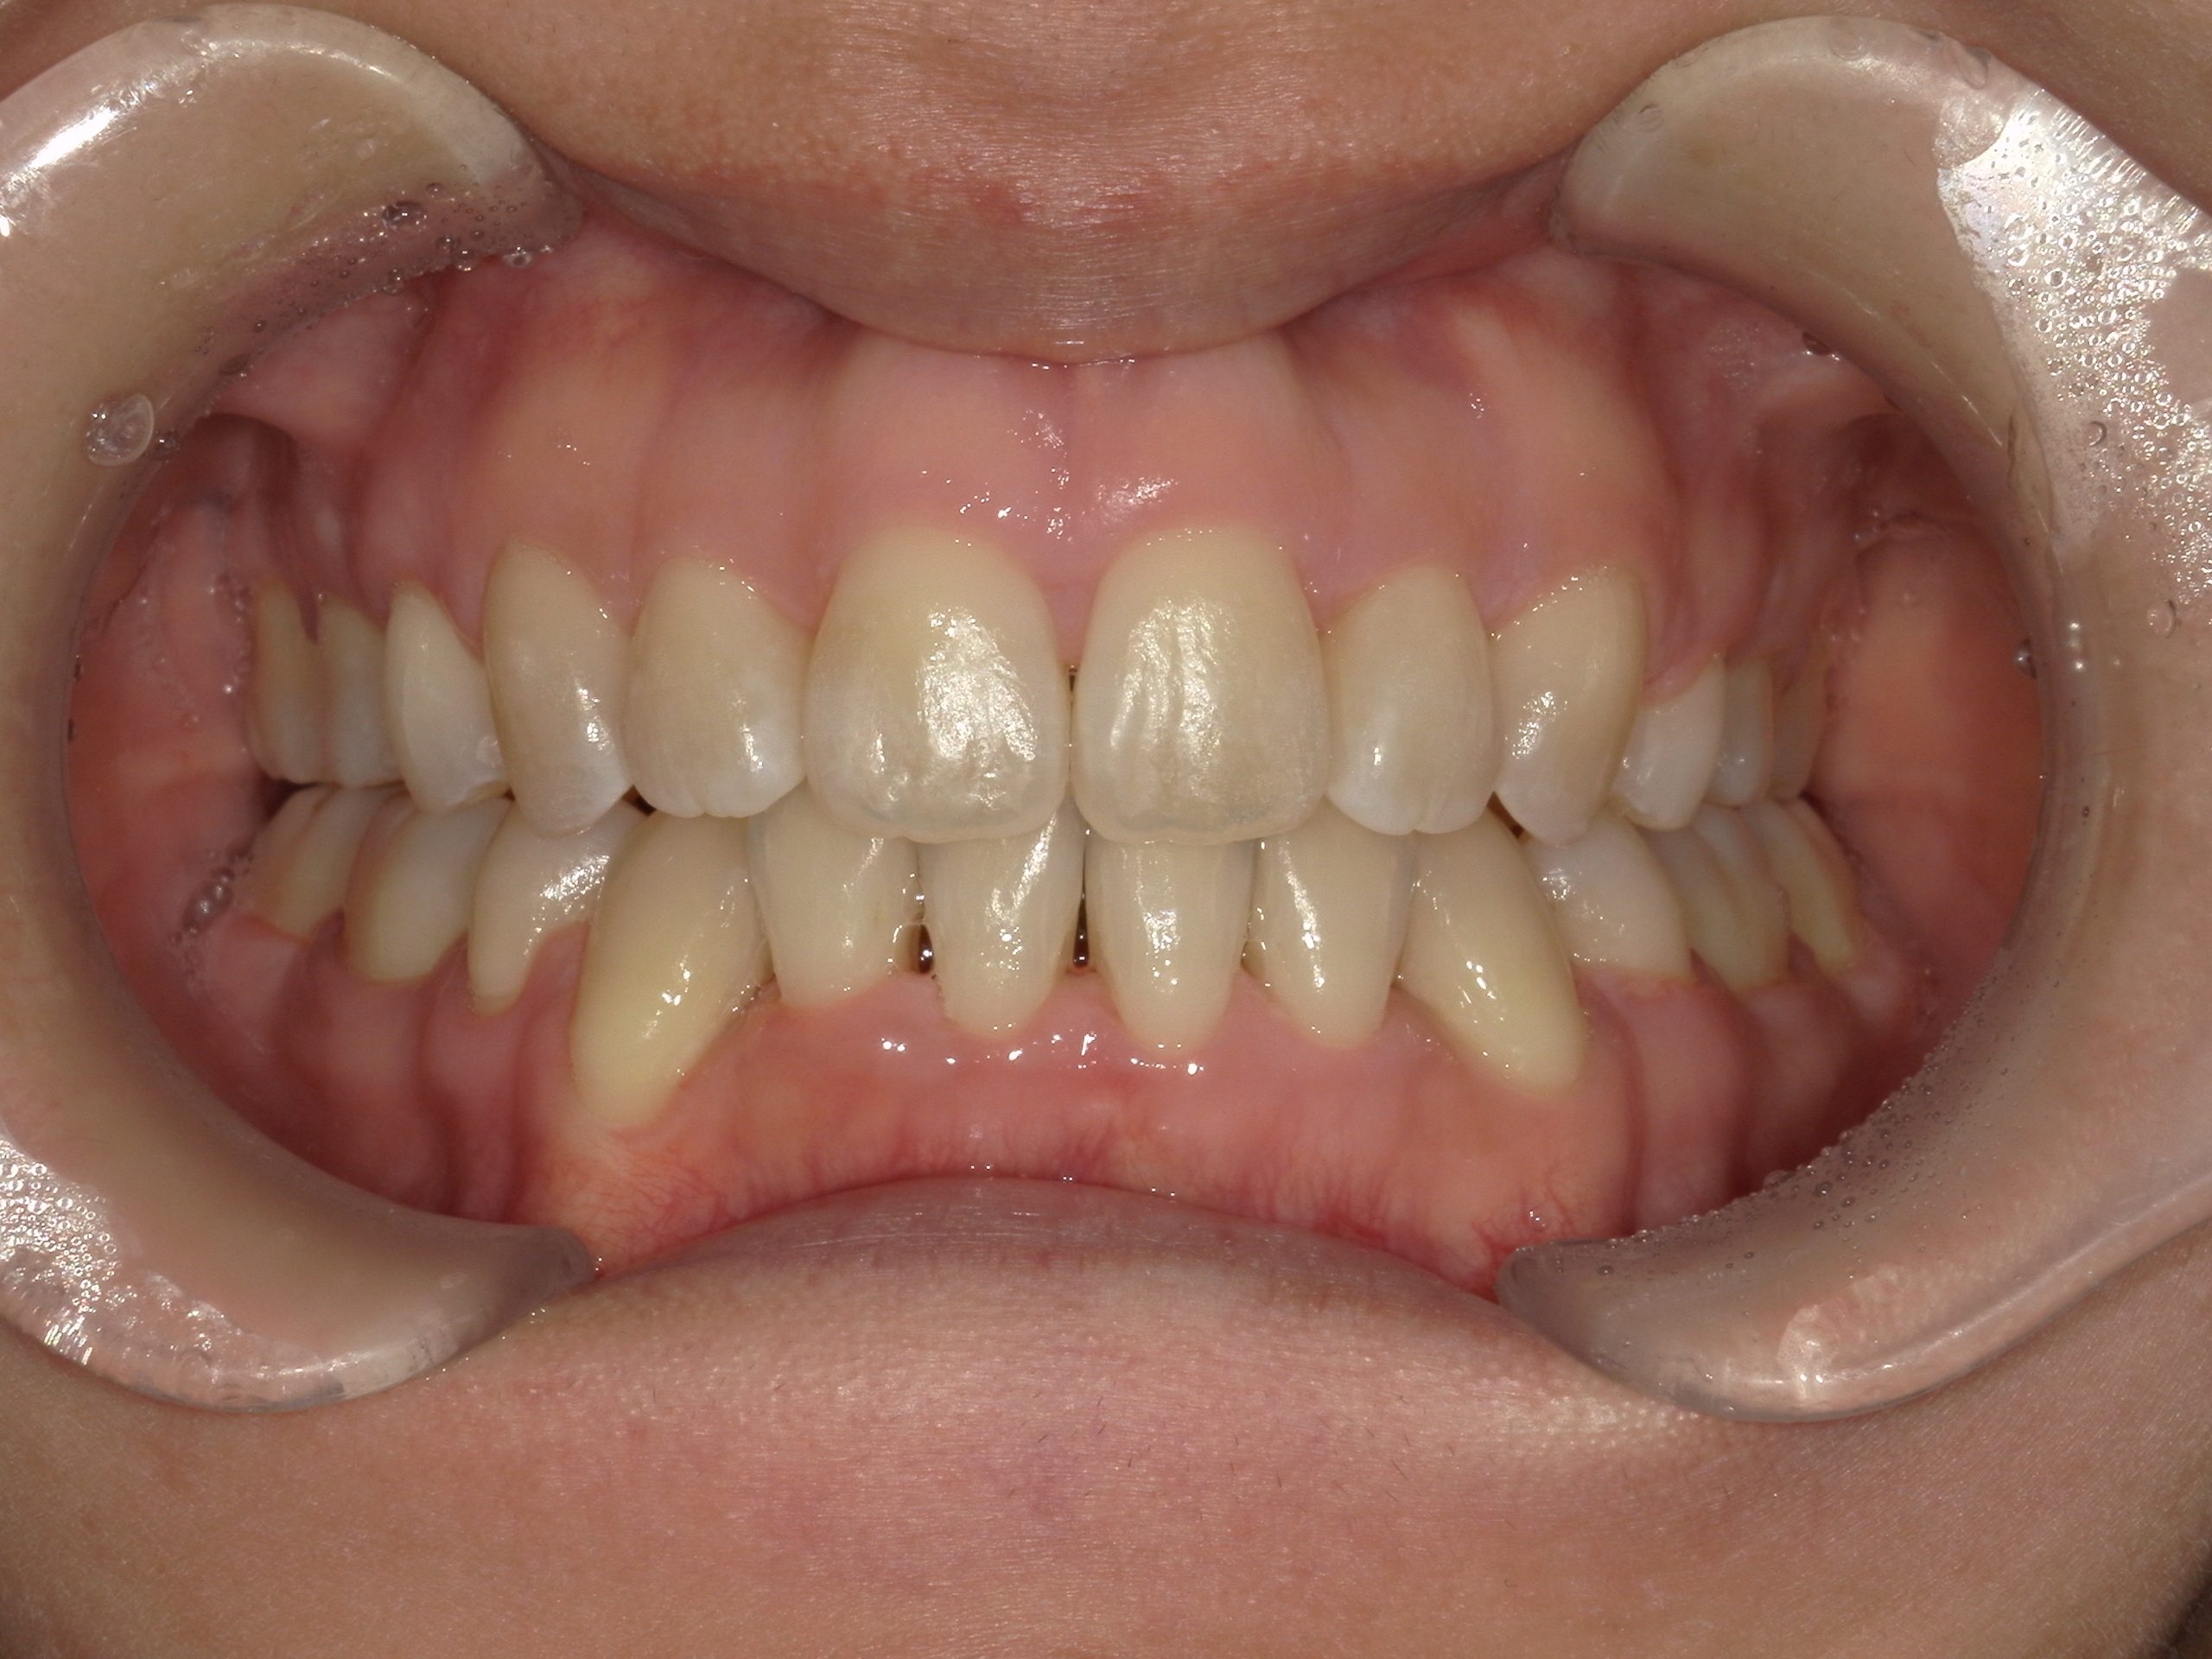

CASE

113上顎前突とガタガタをアンカースクリューを用いた治療で改善した症例

- 年齢

- 35歳

- 主訴

- 出っ歯、口が閉じられない

- 診断名

- 上顎前突、叢生

- 抜歯部位

- 上顎左右第一小臼歯

- 治療期間

- 1年11か月 (2023.11~2025.10)